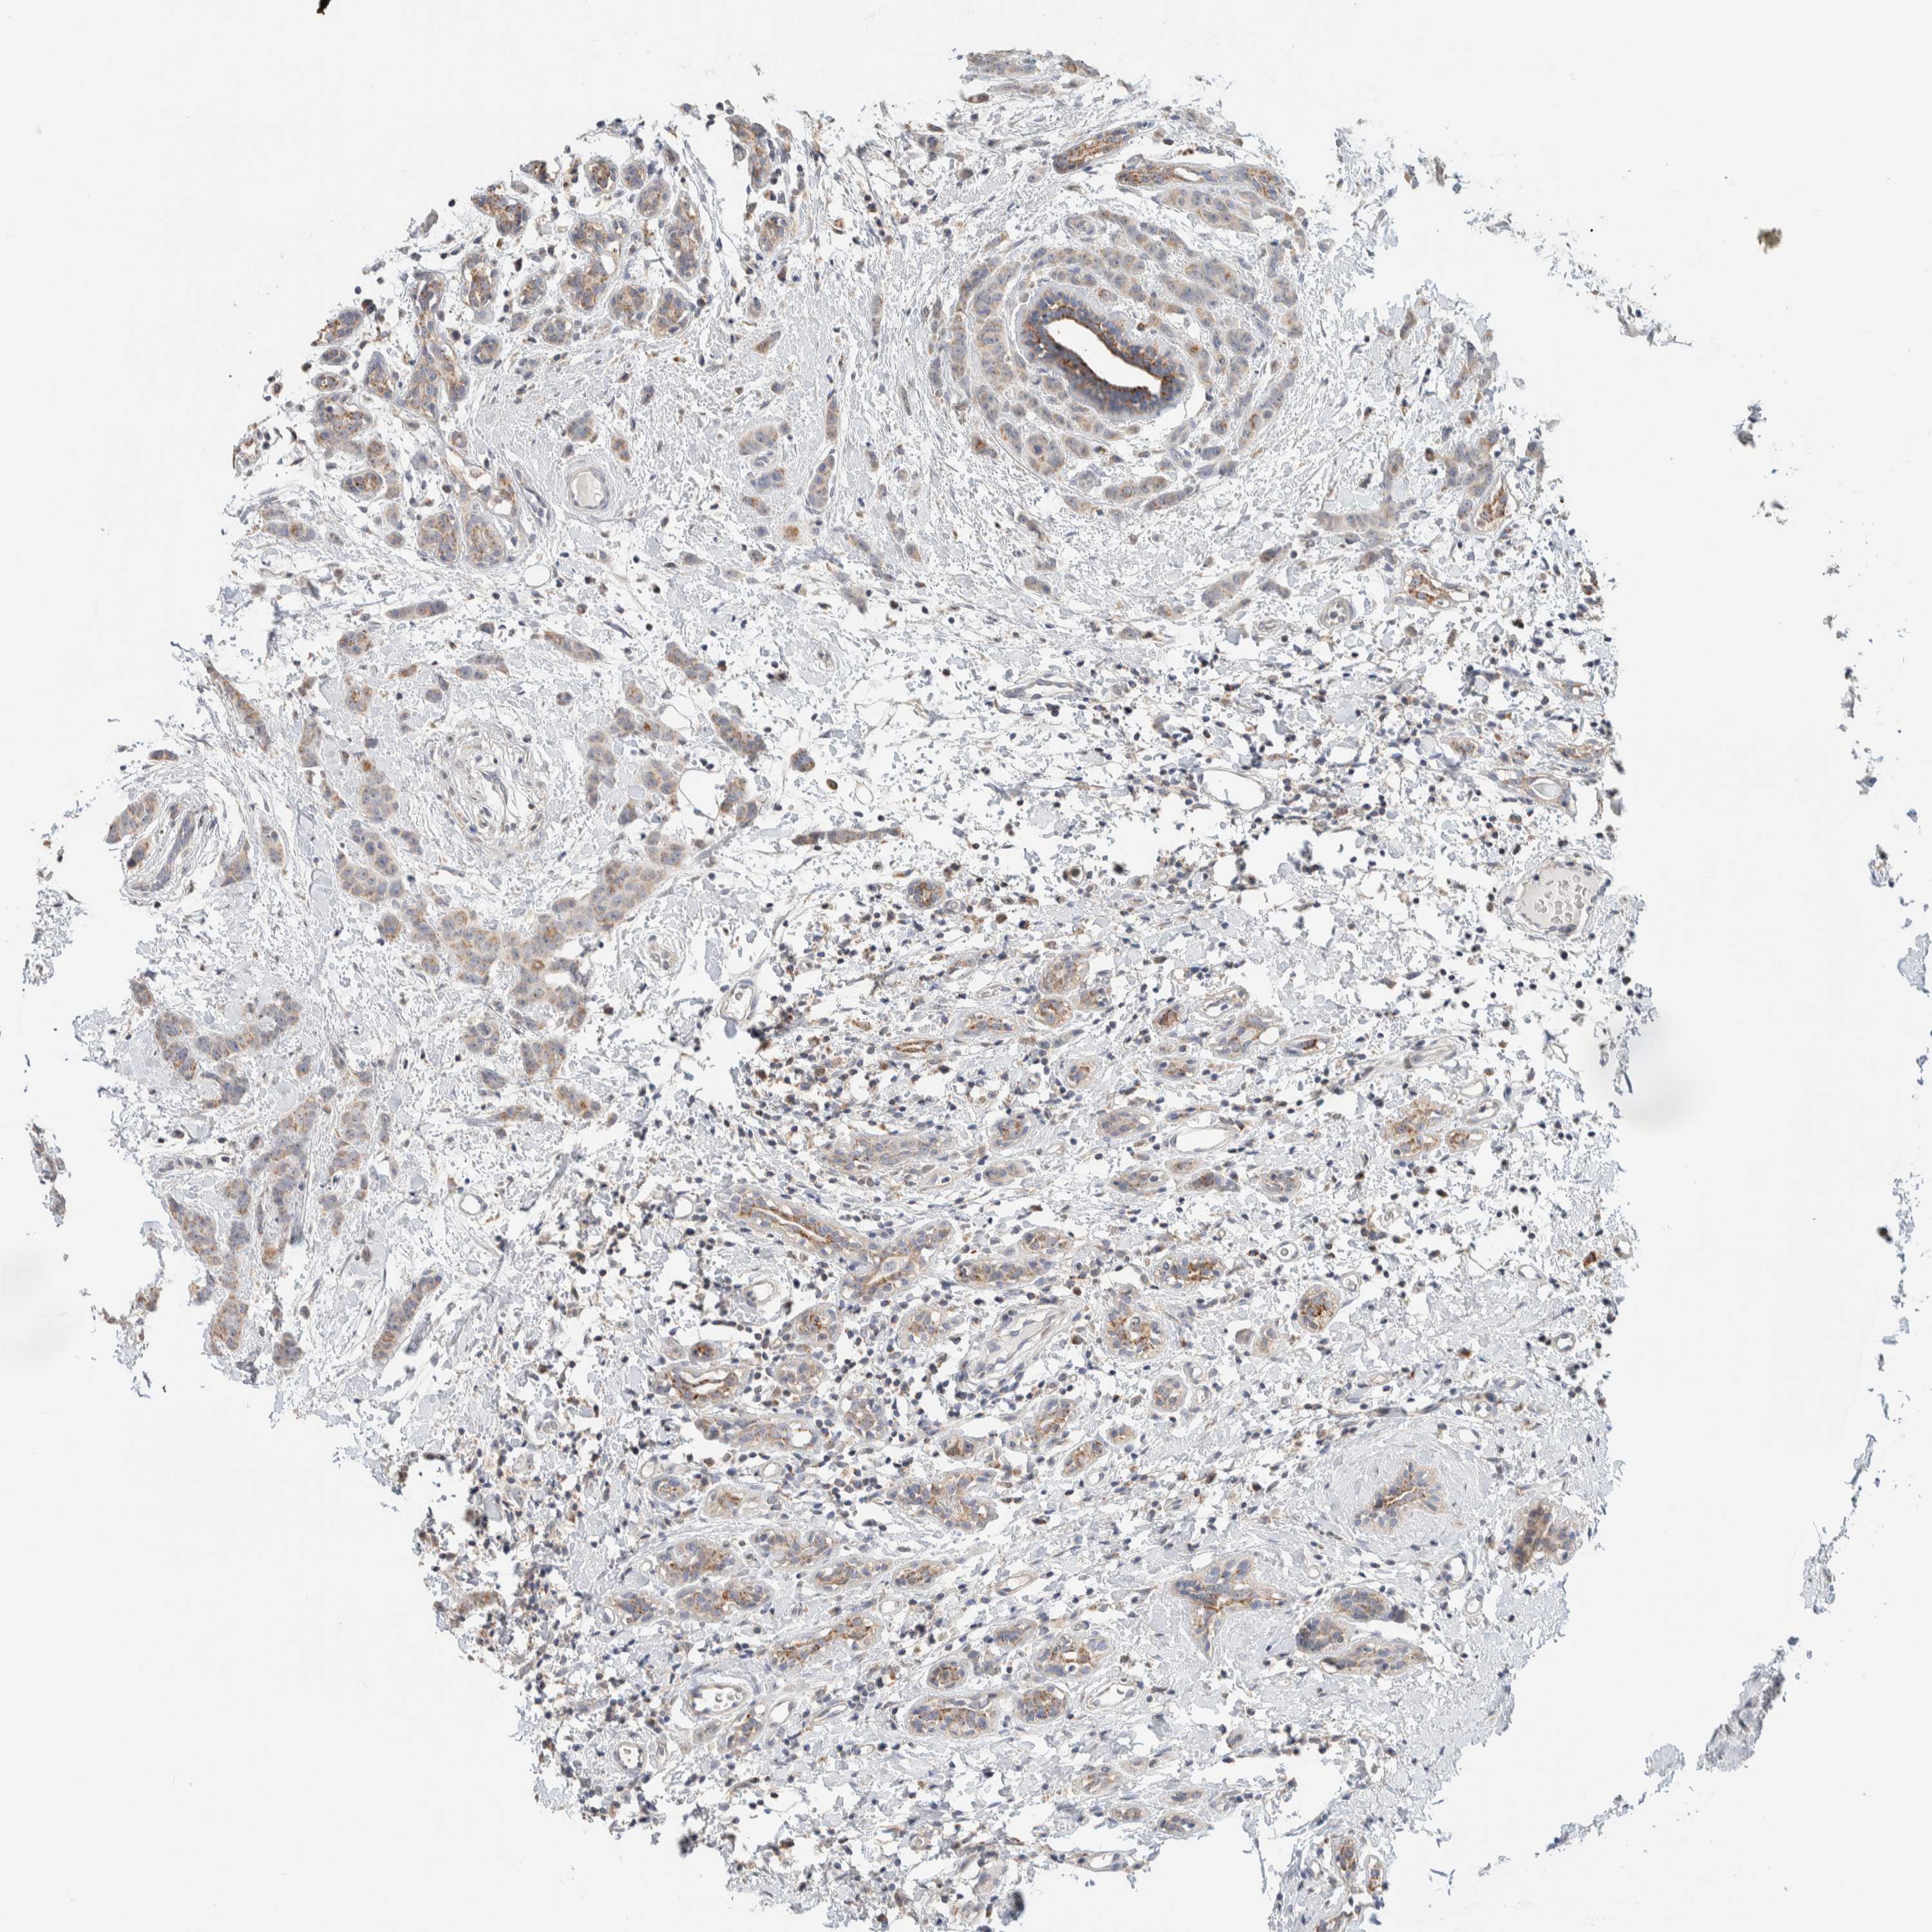

BRCA TCGA BRCA VALIDATION PROTEIN EXPRESSION

Breast cancer

Human cancer